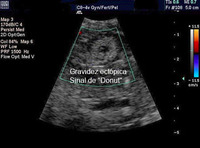

Gravidez ectópica: imagem de ultrassonografia de gravidez ectópica mostrando o sinal de "donut"

Do acervo pessoal de Dra. Melissa Fries, Washington Hospital Center; usado com permissão